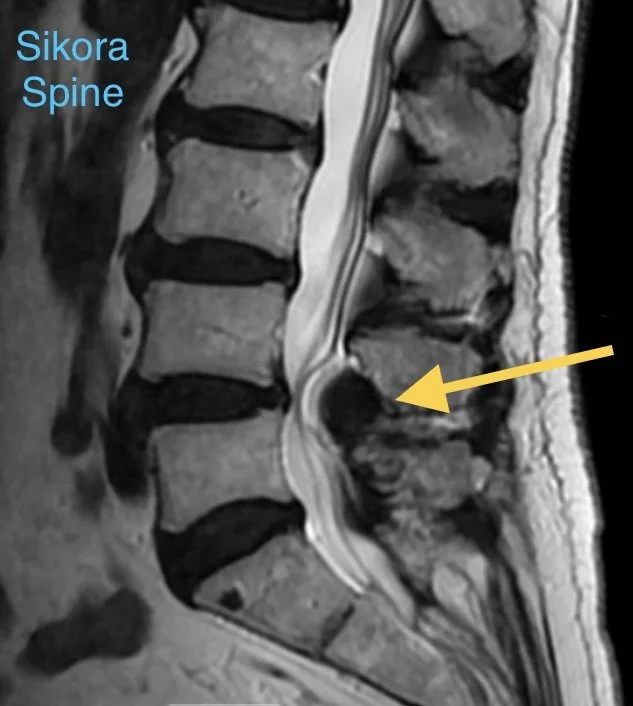

Compression of the nerve sac in the lumbar spine (MRI)

Lumbar Stenosis is when there is narrowing of the area where the nerves run in the back.

If the narrowing is pressing on a nerve(s) it can cause dysfunction, pain, problems with walking, bowel/bladder issues, numbness, and weakness.